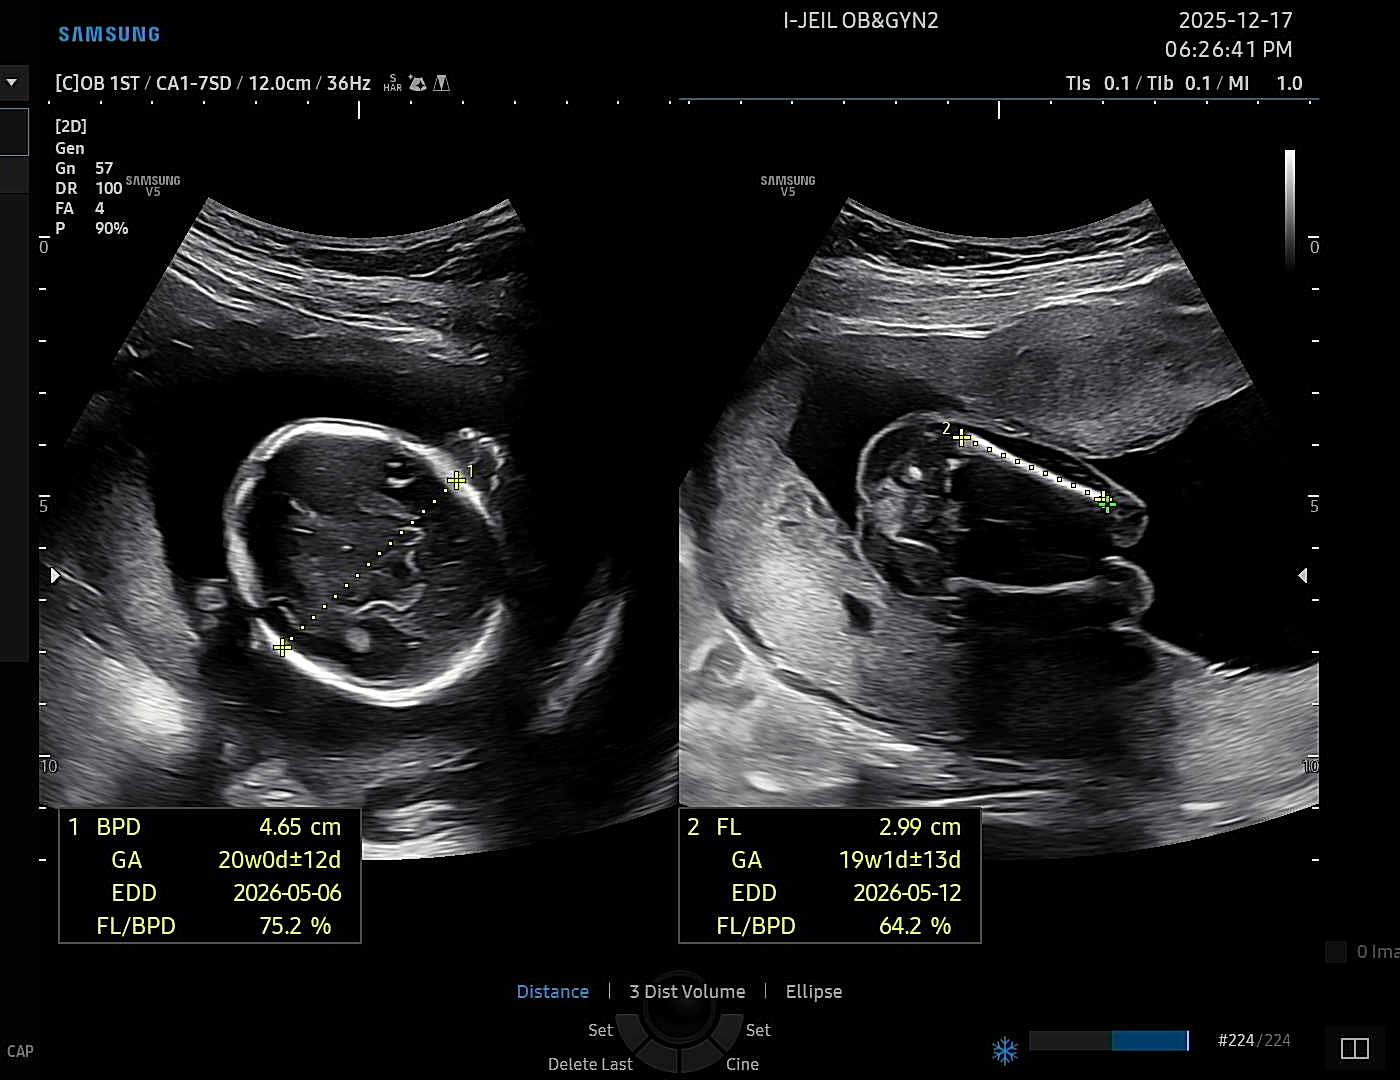

2026년 5월 베동

오늘 19주차 정기검진에서 쌤이 엄마 닮은거 같다구 하셨는데ㅎㅎㅎ 딸맘 당첨인거겟죠?ㅎㅎ